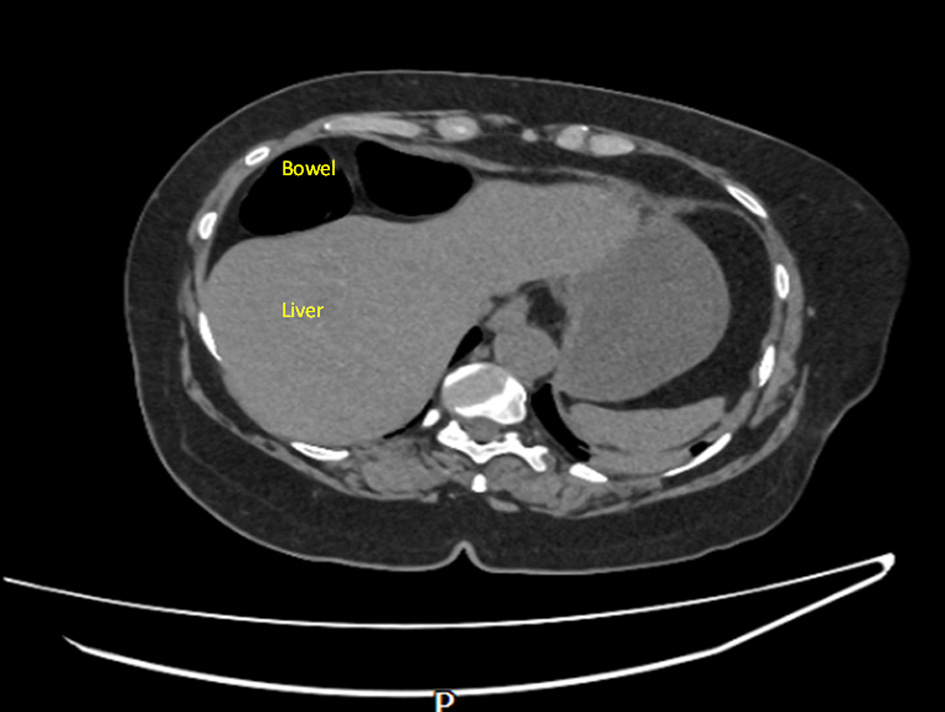

On examination, the patient was found to have externally rotated and shortened left leg and bilateral lower leg edema. Initial abdomen examination revealed soft non-tender abdomen. X-ray imaging of pelvis revealed subcapital fracture of the left neck of femur. She was afebrile (36.4 °C) with heart rate of 68 bpm, oxygen saturation of 97%, and blood pressure of 170/89 mm Hg. On auscultation, the chest was clear bilaterally with a midline trachea and no crepitus. The patient was subsequently diagnosed with non-traumatic neck of femur fracture and underwent hemiarthroplasty of the left leg under general anesthetic. Postoperative examination of the patient revealed soft non-tender but distended abdomen with absent bowel movement. The patient reported no discomfort, but it remains unclear whether this is due to postoperative analgesia or her continuing pregabalin use. Her postoperative analgesia included codeine 30 mg four times a day with breakthrough oral morphine 10 mg as required. The patient opened her bowels on postoperative day 2. Initial supine chest radiograph (CXR) revealed shallow lung expansion with elevated hemidiaphragms more in the right side (Fig. 1), compared with CXR performed 3 years ago which was normal (Fig. 2). Repeat anterior-posterior chest radiograph conducted the second day postoperatively showed gas filled loops of bowel beneath the hemidiaphragms with a distended bowel (Fig. 3). Although pneumoperitoneum was the primary concern, it was crucial to rule this out using both clinical and imaging studies. It remained unclear whether a small bowel obstruction or an abscess was present in X-ray. Computed tomography (CT) was conducted which revealed interposition of bowel between the liver and diaphragm which is consistent with Chilaiditi sign and small compressive atelectasis in the lung basis. The CT scan ruled out the presence of any abnormal bowel dilation, pneumoperitoneum, and abdominal mass (Fig. 4). The patient received medical optimization for bone protection, intensive physiotherapy, and occupational therapy input. She was discharged 13 days postoperatively with twice-daily care support. Reports in her 3-month outpatient orthopedic review remarked on her good recovery. No specific follow-up for her Chilaiditi syndrome was required and her recovery from this was uneventful.

Figure 1. Initial supine chest radiograph (CXR) revealed shallow lung expansion with elevated hemidiaphragms more in the right side. The arrow points towards elevated right hemidiaphragm. Image taken preoperatively.

Figure 3. Anterior-posterior chest X-ray on the day of symptoms beginning showing bilateral gas filled loops beneath both hemidiaphragms more in the right side. The arrow points towards elevated right hemidiaphragm. Images taken day 1 postoperatively.